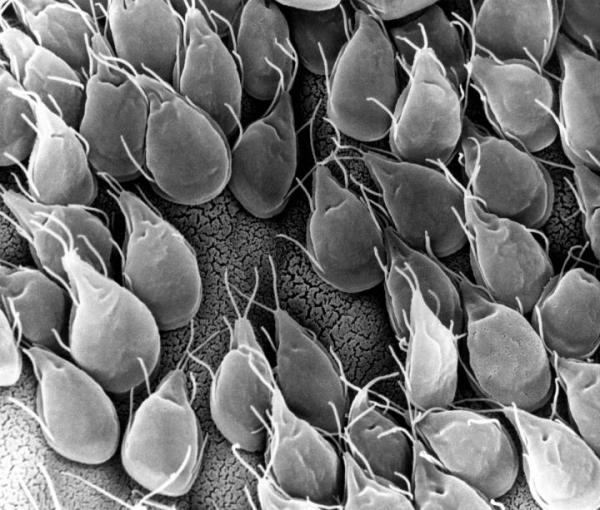

Giardiasis.

Salud unCOMO

La infección del intestino delgado, causada por un parásito transmitido por el agua Giardia lamblia, se llama Giardiasis. Puedes reconocer esta infección por los siguientes síntomas: gases frecuentes, distensión y eructos.